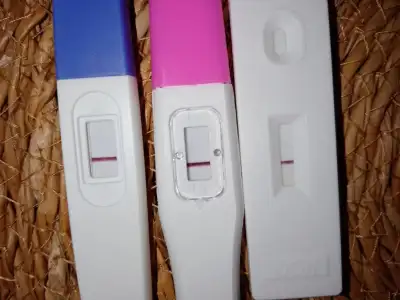

Ben şubatta evlendim . 38 yaşındayım , ilk gebeligim nisanda ve duzensiz beta ile dış gebelik, metotraksat iğne ile düşürüldü, çok üzüldüm, kötü bir süreçti, herkese de söylemiştim çevrem de genistir. Tek tek açıklama yaparken daha da üzüldüm. Şuan 2. Gebeligim 6 Eylül son Regl , 5 hafta4 gün şuan , Regl den 1 hafta önce öğrendim. Erken gebelik testleriyle.sadece Amerika’da 5-6 kişiye söyledim , ailemle paylasmadim, aralıkta gelicem 3 ay dolmuş olacak , sarilarak söylemek istiyorum, tabi içim içime sığmıyor, Erkenden beta ya başladım riskli gebelik olabilir diye, iki kartından fazla artış görüldü ve bir daha yapılmadı, 4. haftalıkken vajinal muayene ile kese de görüldü. Amerika da yaşıyorum burda her gittiğinde farklı dr görüyorsun. 7. Haftada kalp atısına bakilacak. Sizinle de paylaşmak istedim.